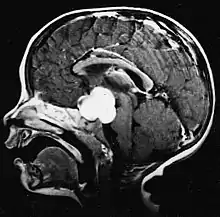

Sur-L'IRM montre une tumeur intracrânienne comme une lésion massive qui peut devenir plus luminescente après utilisation du produit de contraste. Cependant, il y a toujours une anomalie de signal dans -L'imagerie par résonance magnétique, qui indique la présence d'une néoplasie ou d'un œdème vasogénique. Habituellement, une luminescence accrue (amélioration du contraste) indique une tumeur d'un grade supérieur de malignité. Un anneau de contraste est caractéristique du glioblastome, avec la partie luminescente correspondant à la partie vitale de la tumeur maligne, et la plus foncée - zone hypointense correspondant à une nécrose tissulaire.

Glioblastome

Les tumeurs des cellules gliales les plus courantes et les plus malignes sont les glioblastomes. Ils consistent en une masse hétérogène de cellules d'astrocytome peu différenciées principalement chez l'adulte. Ils surviennent généralement dans les hémisphères cérébraux, plus rarement dans le tronc cérébral ou la moelle épinière. Sauf dans de très rares cas, comme toutes les tumeurs cérébrales, elles ne s'étendent pas au-delà des structures du système nerveux central.

Le glioblastome peut provenir d'une forme diffuse (II. grade) ou un astrocytome anaplasique (III. grade) développer. Dans ce dernier cas, il est dit secondaire. Cependant, lorsqu'elle survient sans antécédent ni signe de malignité antérieure, on parle de maladie primaire. Les glioblastomes sont traités par chirurgie, radiothérapie et chimiothérapie. Ils sont difficiles à guérir et rares sont les cas qui survivent au-delà de trois ans.